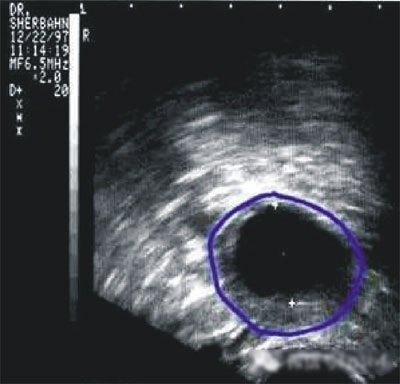

陰道B型超聲動態監測卵泡的發育及排卵,是監測排卵最準確可靠的方法。通過陰道B超檢查可以了解子宮及雙側附件(卵巢和輸卵管)區的基本情況,測定卵巢內的竇卵泡計數,評估卵巢儲備功能,動態監測排卵。